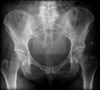

Intracapsular (Garden classification)

Intracapsular NOF fracture Garden classification type I

Intracapsular NOF fracture Garden classification type II

Intracapsular NOF fracture Garden classification type III

Intracapsular NOF fracture Garden classification type IV